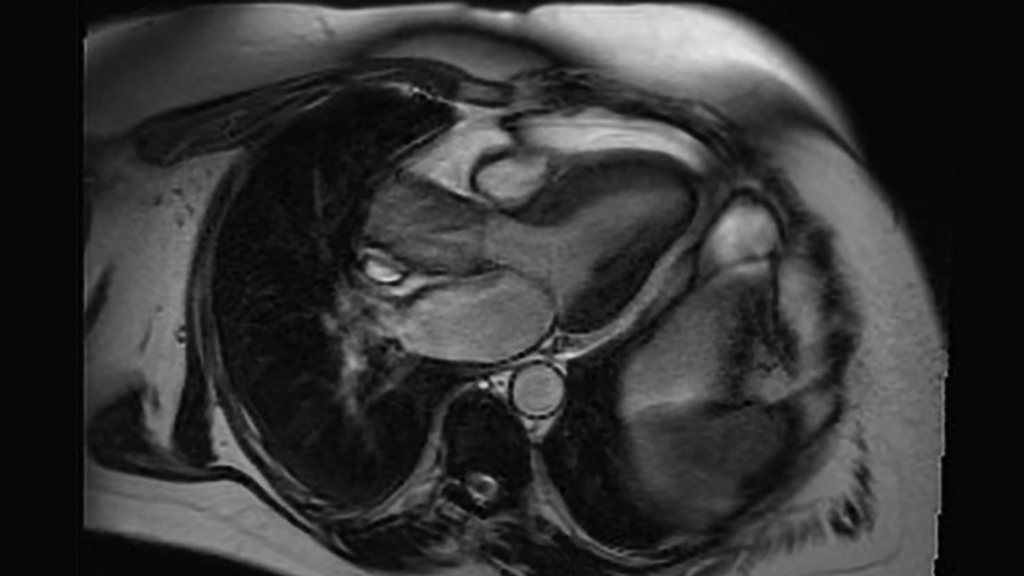

A CT scan depicts a bicuspid aortic valve and aortic stenosis

Aortic valve stenosis presenting with bicuspid aortic valve.